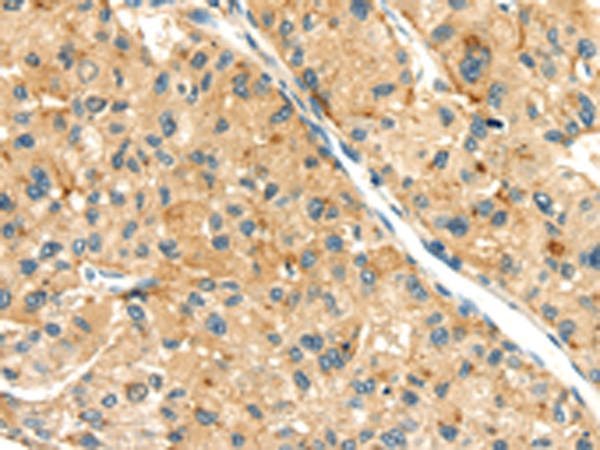

分类: 科研抗体货号: P08752别名: SEMAF; SEMAI; SEMACL1; M-SEMA-F应用: IHC反应种属: Human, Mouse